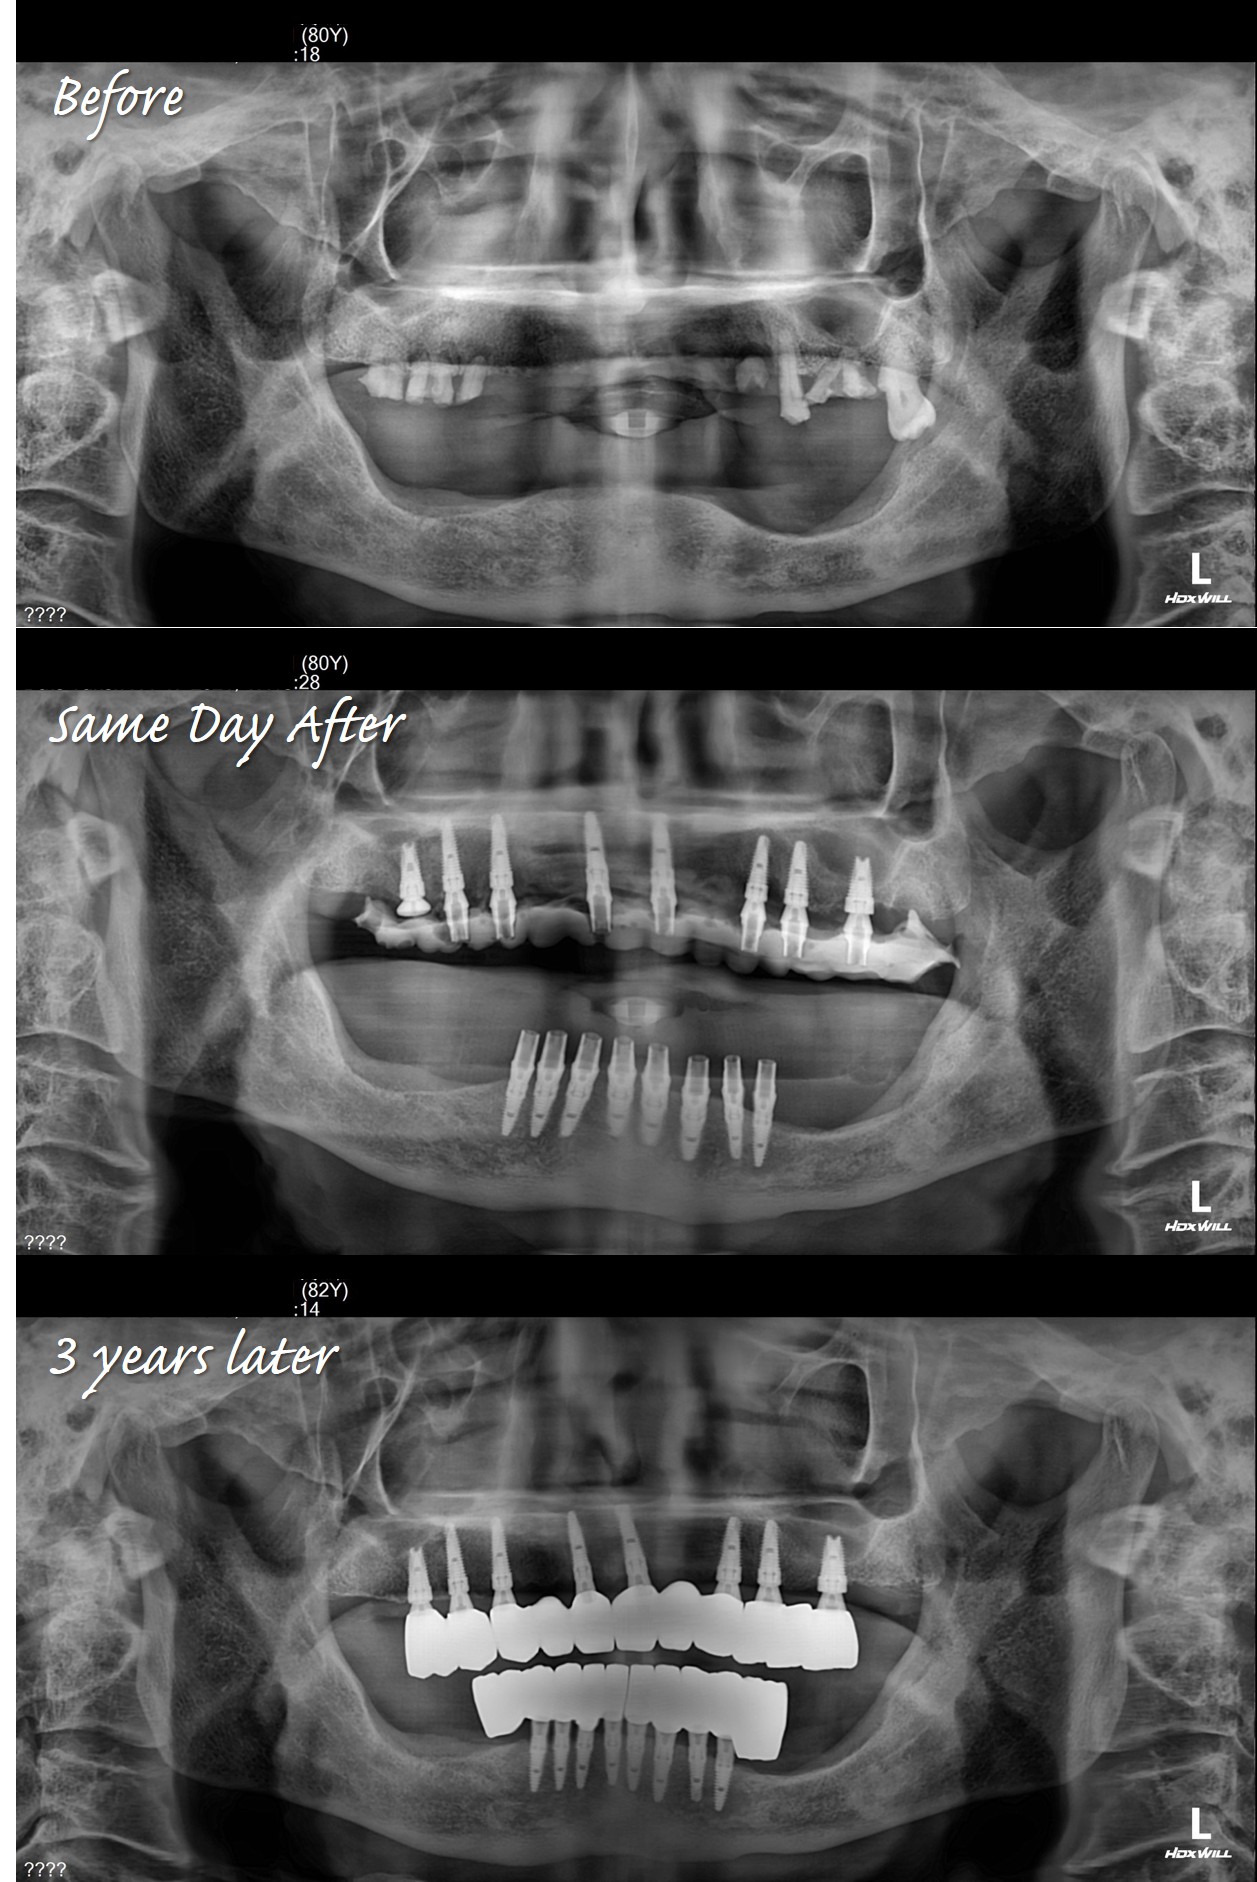

我剛開始接觸一鑽植牙系統不久,就有幸觀摩到陳博士與本診所負責人鄭醫師,攜手完成的一例全口重建手術。這位年逾八十的老先生,在子女的鼓勵下,終於下定決心接受一次到位的全口植牙手術。

手術過程中,陳博士從容不迫地先行植入上顎,再進行下顎植體安置;同時,原有的全口假牙也被妥善當作參考,作為臨時假牙與日後製作永久固定假牙的重要依據。在這個案例中,我深刻體會到一鑽系統與專用鼻竇專用植體的卓越效率──陳博士以 free-hand 方式精準定位,僅用一個多小時便完成上、下顎共16顆植體-上顎8根與下顎8根的植入手術;一鑽植牙初期穩定度非常高,所以術後立即配戴臨時假牙,當日即可進食,充分展現「五合一」技術。

如今,患者已使用永久假牙三年多,且陳博士累積數千例全口重建的成功經驗與患者回饋,更證實了此治療方案的可靠與正確。我也期許自己能朝著陳博士的專業目標持續精進,為更多患者帶來福祉。